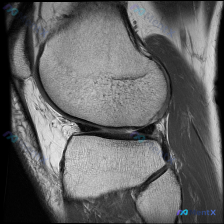

给大家分享一个很有启发的膝关节MRI读片病例,临床关注点是半月板异常,读完片发现其实核心问题不在这儿,整理一下完整分析思路。 病例影像基本信息 这是一份膝关节矢状位T2加权MRI(压脂序列),我们先整理所有客观发现: 1. 关节内结构:半月板形态完整,呈典型低信号三角表现,未见贯穿性高信号,边缘光滑...

看到一个很典型的临床-影像矛盾病例,整理出来和大家分享思路。 病例核心信息 这是一张膝关节矢状位MRI单张图像,临床关注点为「半月板异常」,我们先来看影像的全面评估结果: 1. 骨骼结构:股骨远端、胫骨近端、髌骨轮廓完整,无明显骨皮质中断或骨折 2. 关节软骨:股骨、胫骨关节面软骨信号均匀,无明显剥...

刚整理了一份有意思的影像读片病例,和大家分享一下思路。 病例基本信息 本次仅提供放射影像-膝盖MRI-T1序列-矢状位单张图像,核心问题是询问图像中是否存在半月板异常。 影像学读片结果 我仔细读了这张片子,所有结构的情况如下: 1. 骨骼结构:股骨远端、胫骨近端、髌骨的骨皮质连续,骨髓信号正常,没有...